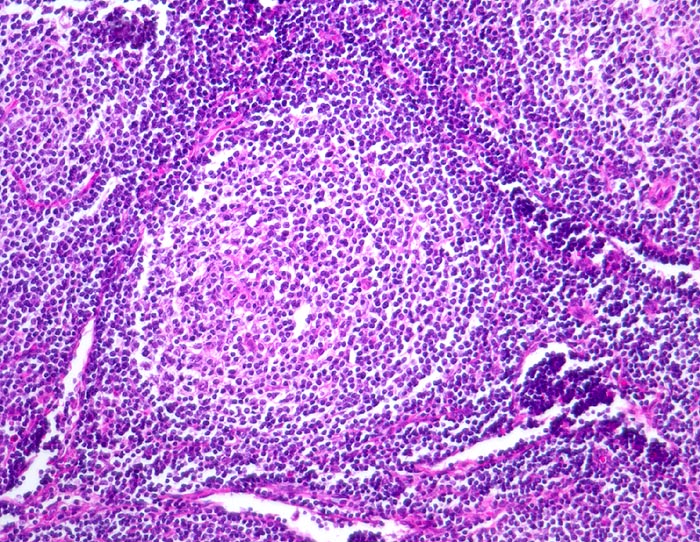

Follikuläres B-Zell Non-Hodgkin-Lymphom

Neoplastischer Follikel mit unscharfer Begrenzung. Eine dunklere Mantelzone ist nicht erkennbar. Das Follikelzentrum ist auffallend monoton. Es fehlen die Kerntrümmermakrophagen, welche für reaktive Keimzentren typisch sind.

Die Keimzentren sind immunhistochemisch positiv für bcl-2.